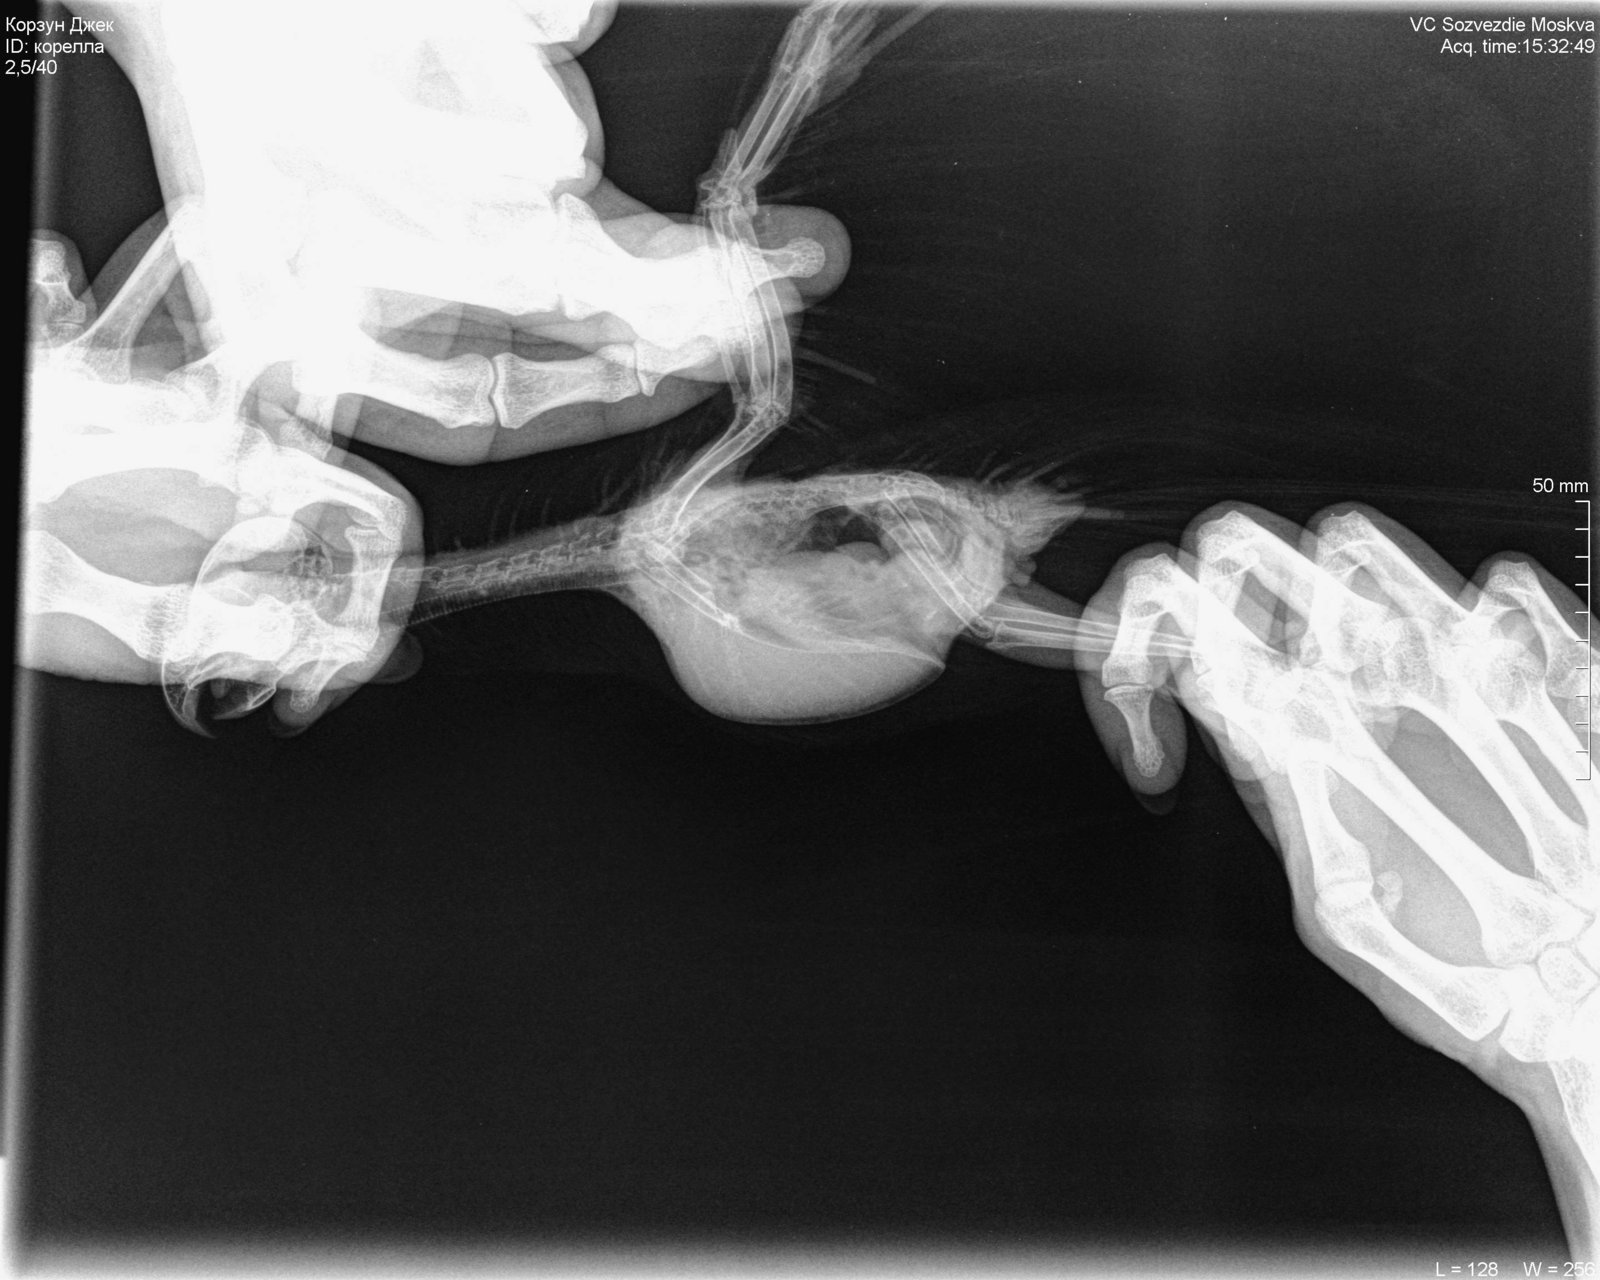

Здравствуйте, корелла самка , возраст 1 год 1 месяц. Вес 100 гр. Поведение - активная , ест, пьет. Оперение нормальное. Питание - овощи, фрукты даю, но практически не ест, каша без молочная детская, чумиза, есть копошилка, сепия, минеральный камень, скелетин с серой, бентонит кормовой, Рио для средних попугаев. Уф лампа есть , световой день 12-13 часов. Весь день летает. Взята была девочка у заводчика в возрасте 3 месяцев, заводчик настойчиво рекомендовала давать песок Рио и рисовую кашу и гречку с желтком яйца, что я и делала 4 раза в неделю, потом я выяснила, что это давать нельзя, и сразу же все убрала и не даю уже около месяца. Первые подозрения на плохое самочувствие были на постоянные вытягивания шеи, иногда трясет головой, умывается очень часто, делая при этом нервные движения при очистке Перьев. Самый основной симптом жидкий помет практически всегда. 12 августа она снесла яйцо ночью, утром я сразу же его выкинула и отвезла к орнитологу. При осмотре орнитологом она сказала , что деформированы носовые ходы , ожирение. Рекомендован был рентген, по рентгену орнитолог сказала , что к попугая : Аэросаккулит(воспаление воздушных мешков), пневмония, нефрит, гепатомегалия, повышенная плотность костей связана с гиперестрогенизмом Были сданы анализы , пока еще не готовы , один готов , вот результат: Цвет: светло-зеленый Консистенция: жидкий Соотношение микроорганизмов: подвижные кокки 50%, палочки 50%, стрептококки Кристаллы мочевой кислоты в большом количестве Нейтральный жир умеренно Билирубин отсутствует Жирные кислоты отсутствуют Соли жирных кислот отсутствуют Крахмал внеклеточный в большом количестве Крахмал внутриклеточный отсутствует Лейкоциты более 10 в поле зрения Эритроциты более 20 в поле зрения Эпителий клоаки в большом количестве Эпителий кишечный в большом количестве Слизь присутствует Дрожжи в большом количестве Простейшие не обнаружено было назначено лечение: Амоксиклав/ Флемоклав/ Экоклав (250 мг) - 1 таблетку растворить в 3 мл воды, давать / 0.2 мл, каждые 12 часов в течение месяца. Целекоксиб (200 мг) 1 капсулу растворить в 10 мл воды, давать по 0.05 мл в клюв 1 раз сутки в течение 14 дней Тербинафин таблетки 250 мг - 1 таблетку растворить в 5 мл воды, давать по 0.03 мл 1 ра в 24 часа в течение месяца. Кальций глюконат 100 мг/мл по 2-3 мл в поилку на 50 мл воды 15 дней. Гептрал/Самеликс в обычной аптеке 400 мг/5 мл по 0.1 мл в день месяц Если здесь есть орнитологи, прошу помогите пожалуйста, я была на консультации 3 врачей, я боюсь давать своей птичке Амоксиклав и тербинафин целый месяц. Не много ли это ? Как вы считаете ? И пожалуйста посмотрите рентген умоляю, скажи , что вы видите ? Насколько плохой анализ помета ? И насколько серьезны поставленные диагнозы? И возможно ли это вылечить? Остальные анализы как придут, я приложу фотографии.